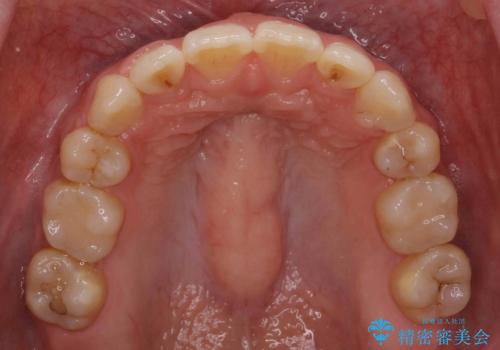

治療の難易度としてはかなり高めでしたが、無事終了することができました。